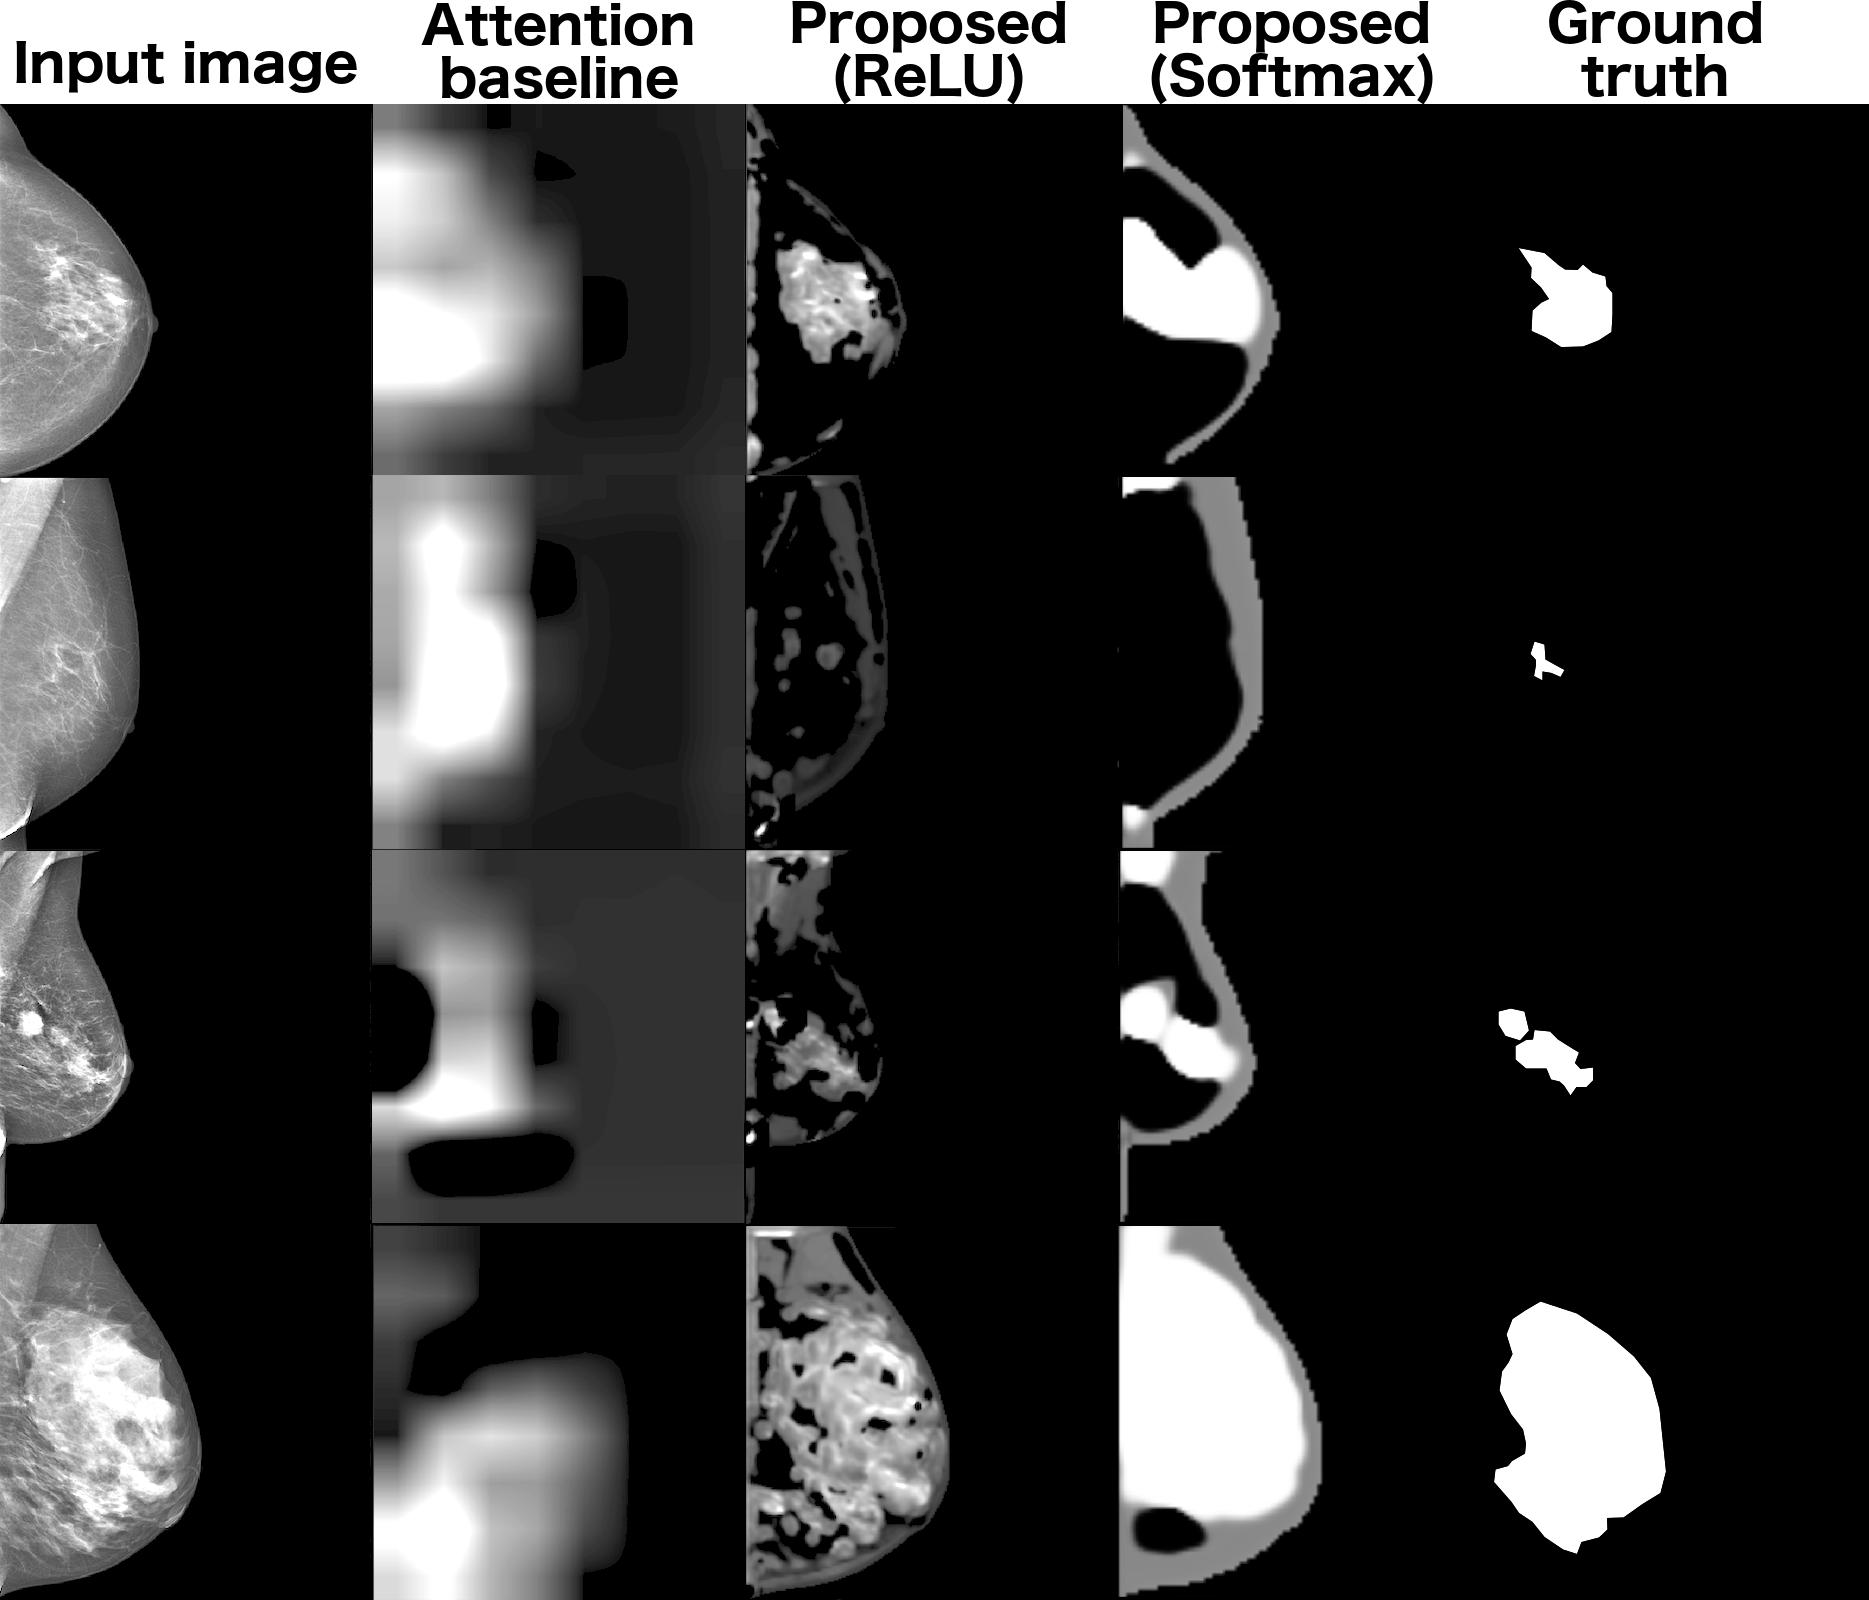

To validate the segmentation performance, we collected regions of interest on several images (16) and calculated the . Overall we obtain clinically meaningful segmentation masks offering valuable insights into the spatial distribution of the dense tissues (fig. LABEL:fig:dense_masks). In comparison, we demonstrate the inefficiency of the attention-based techniques for the breast density mask generation.

fig:dense_masks